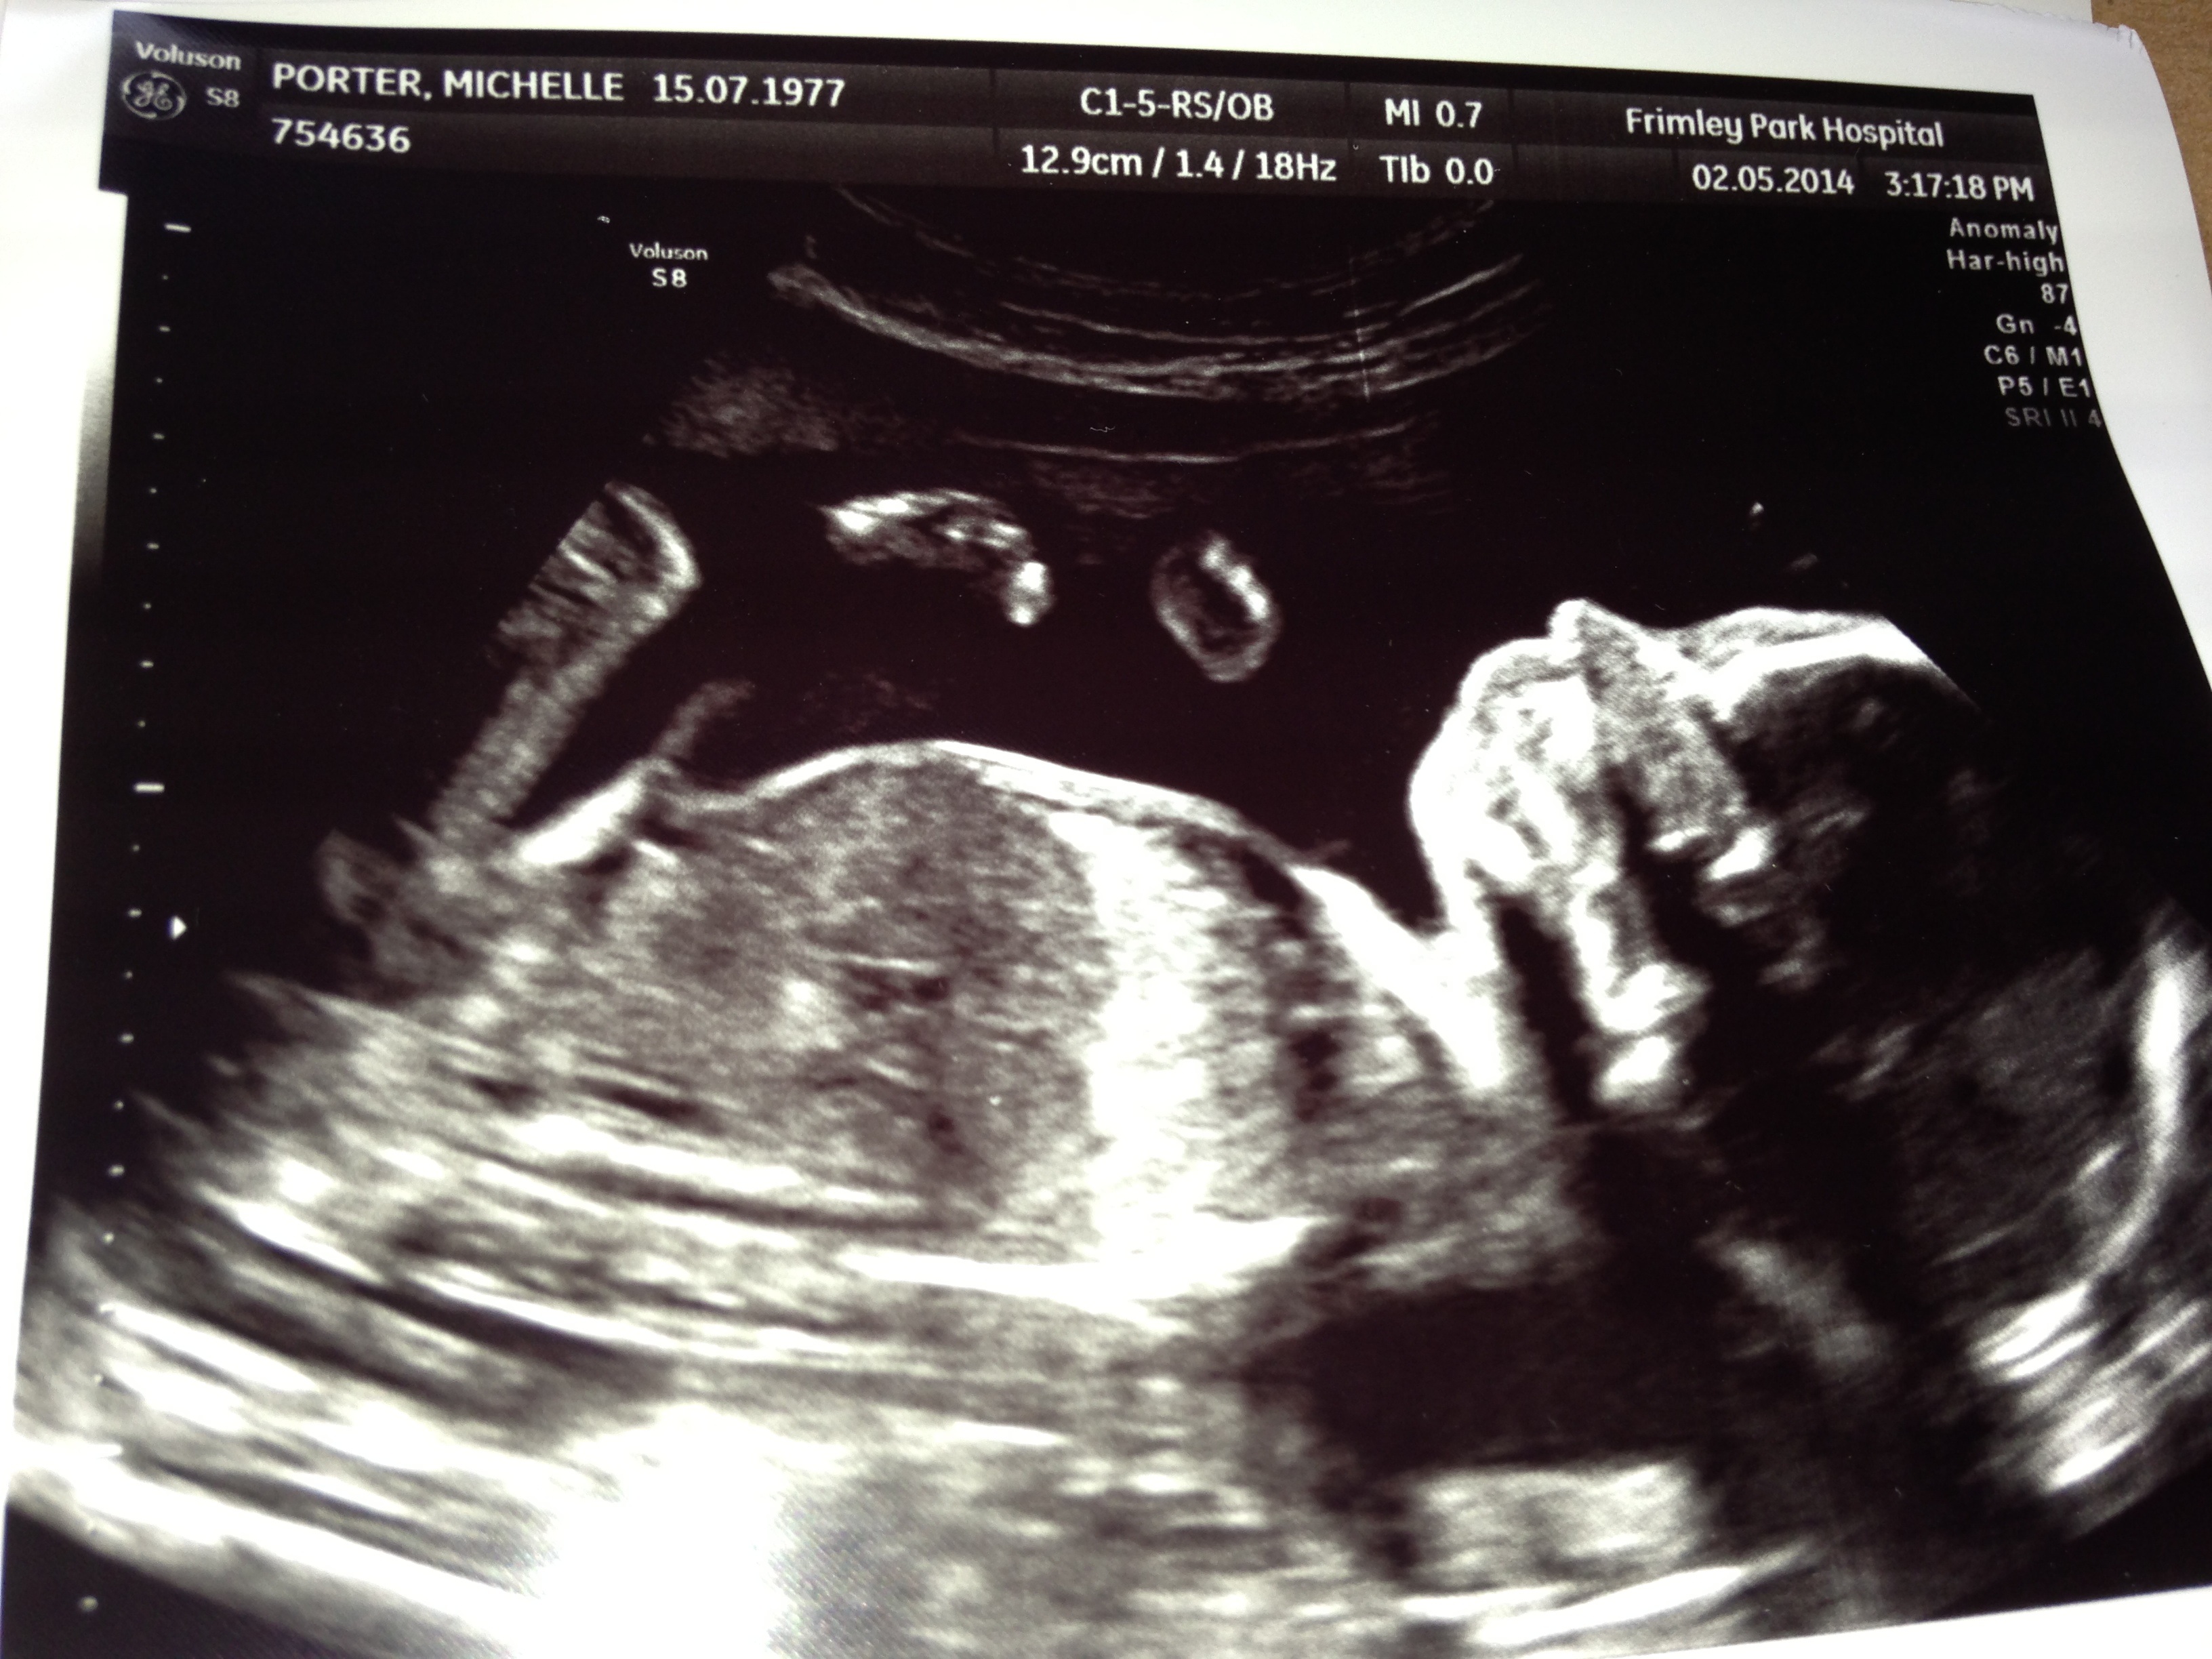

Hi this is my 20 week scan- any gender clues?Attachment 19713

I'm pretty sure there is an obvious turtle shape behind first leg?

So I was supposed the doctor gave me a pic where it seems very obvious- if the turtle shape behind first leg isn't boy bits then what could it be?

My midwife confirmed today that based on the pic it very much looks like a boy. Are we seeing something you guys don't? If I knew how to circle the bit I see I would- it's the fuzzy shape sticking out bottom left of image just below first leg bone